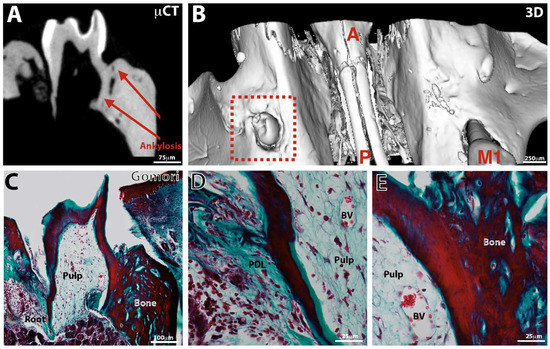

3.3. Tooth Eruption